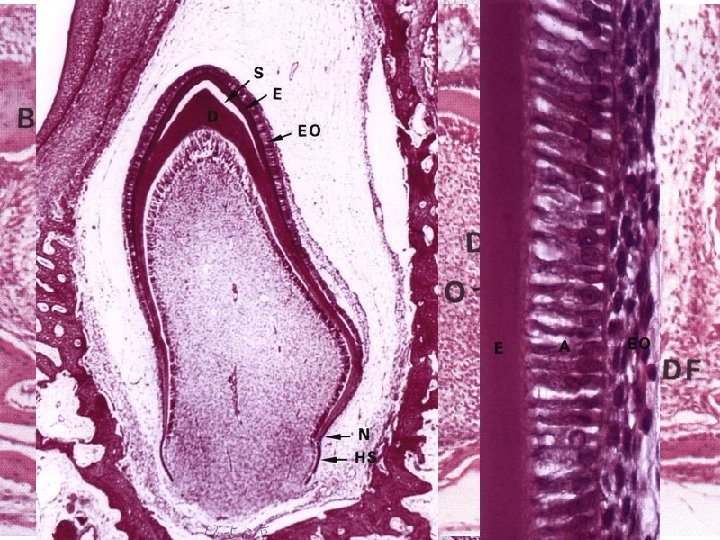

Vývoj zubů 6. týden: proliferace orálního epitelu (ektodermu) do okolního ektomezenchymu • zubní lišta (rovnoběžně s labiogingivální lištou) • ektoderm → sklovinný orgán – vnější sklovinný epitel – stratum intermedium, retikulární epitel – vnitřní sklovinný epitel (ameloblasty) • ektomezenchym → zubní papila (odontoblasty) • cervikální smyčka

Vývoj zubů • tvorba dentinu – odontoblasty: prokolagen → predentin → dentin • při ústupu před svým produktem zanechávají výběžky v dentinových kanálcích (Tomesova vlákna) • tvorba skloviny – bazální povrch ameloblastů se stává sekrečním: • sklovinná matrix (organická – mineralizace) • vývoj kořenů • cervikální smyčka (kořenová pochva) • po jejím rozpadu indukuje dentin vznik cementoblastů • stálý chrup • sekundární zubní lišta linguálně od primární

Vývoj zubů Thomas W. Sadler, Langmanova lékařská embryologie, překlad 10. vydání, Grada Publishing, a. s. 2011